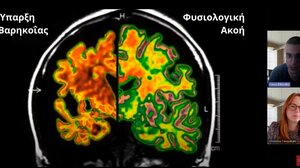

Οι επιπτώσεις της βαρηκοΐας στον εγκέφαλο και οι λύσεις για παιδιά και ενήλικες ΥΓΕΙΑ 24.07.2024Οι επιπτώσεις της βαρηκοΐας στον εγκέφαλο και οι λύσεις για παιδιά και ενήλικες